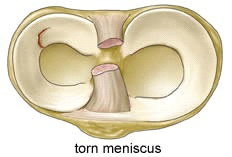

Meniscus letsels

Kunnen ontstaan door een ongeval (posttraumatisch) of door slijtage (degeneratief)

Gezien de functie van de meniscus (optimalisatie van de gewichtsverdeling tussen het boven en het onderbeen) is het impact van deze letsels ( zeker bij jonge patiënten) niet te onderschatten daar deze letsels kunnen leiden tot vervroegde slijtage van het kraakbeen (artrose)

De behandeling van dergelijke letsels is, afhankelijk ook van het type letsel en de leeftijd van patiënt, zo behoudend (conservatief) mogelijk en kan bestaan uit een arthroscopische(via kijkoperatie)

meniscushechting

Zo beperkt mogelijke (partiële) meniscus resectie.

Meniscus transplantatie in specifieke gevallen.